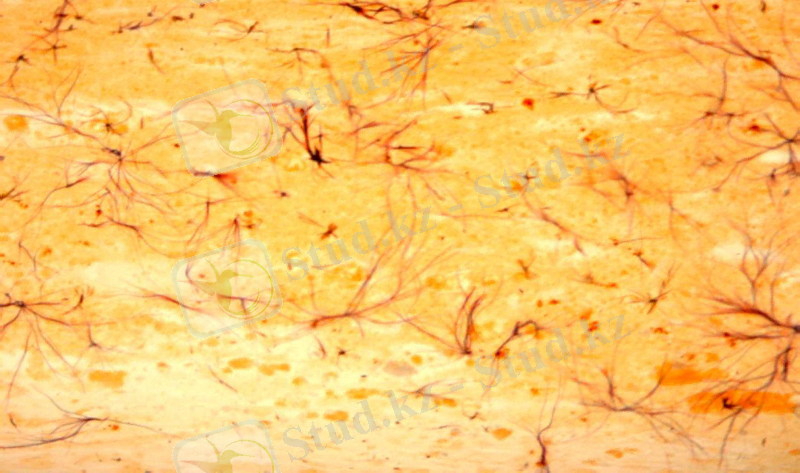

1 сурет. Мукоидты ісіну

Мукоидты ісіну - дәнекер ұлпасының үстіртін және қайтымды зақымдалуы. Бұл кезде дәнекер ұлпасының негізгі затында гликозамингликандар ыдырап, гиалурун қышқылы көбейеді.

Микроскопиялық көрінісі . Микроскоп арқылы ұлпаның бояу сіңіру қасиетінің өзгергеніне көз жеткізуге болады: тіліндіні гемотоксилин-эозинмен бояғанда торшааралық негізгі зат көкшіл тартады, ал толуидин көгімен ұлпа қызғылт түске боялады, яғни, метахромазияға ұшырайды.

Процеске тән қасиеттер. Зақымданған ұлпа мен мүшенің сыртқы көрінісі өзгермейді. Бұл процеске тән өзгерістер тек гистохимиялық реакциялар арқылы анықталады. Мукоидтық ісіну әртүрлі мүшелер мен ұлпаларда кездесетін процесс, көбінесе артериялар қабырғаларын, жүрек қақпақшаларын, эндокардты, эпикардты зақымдайды.